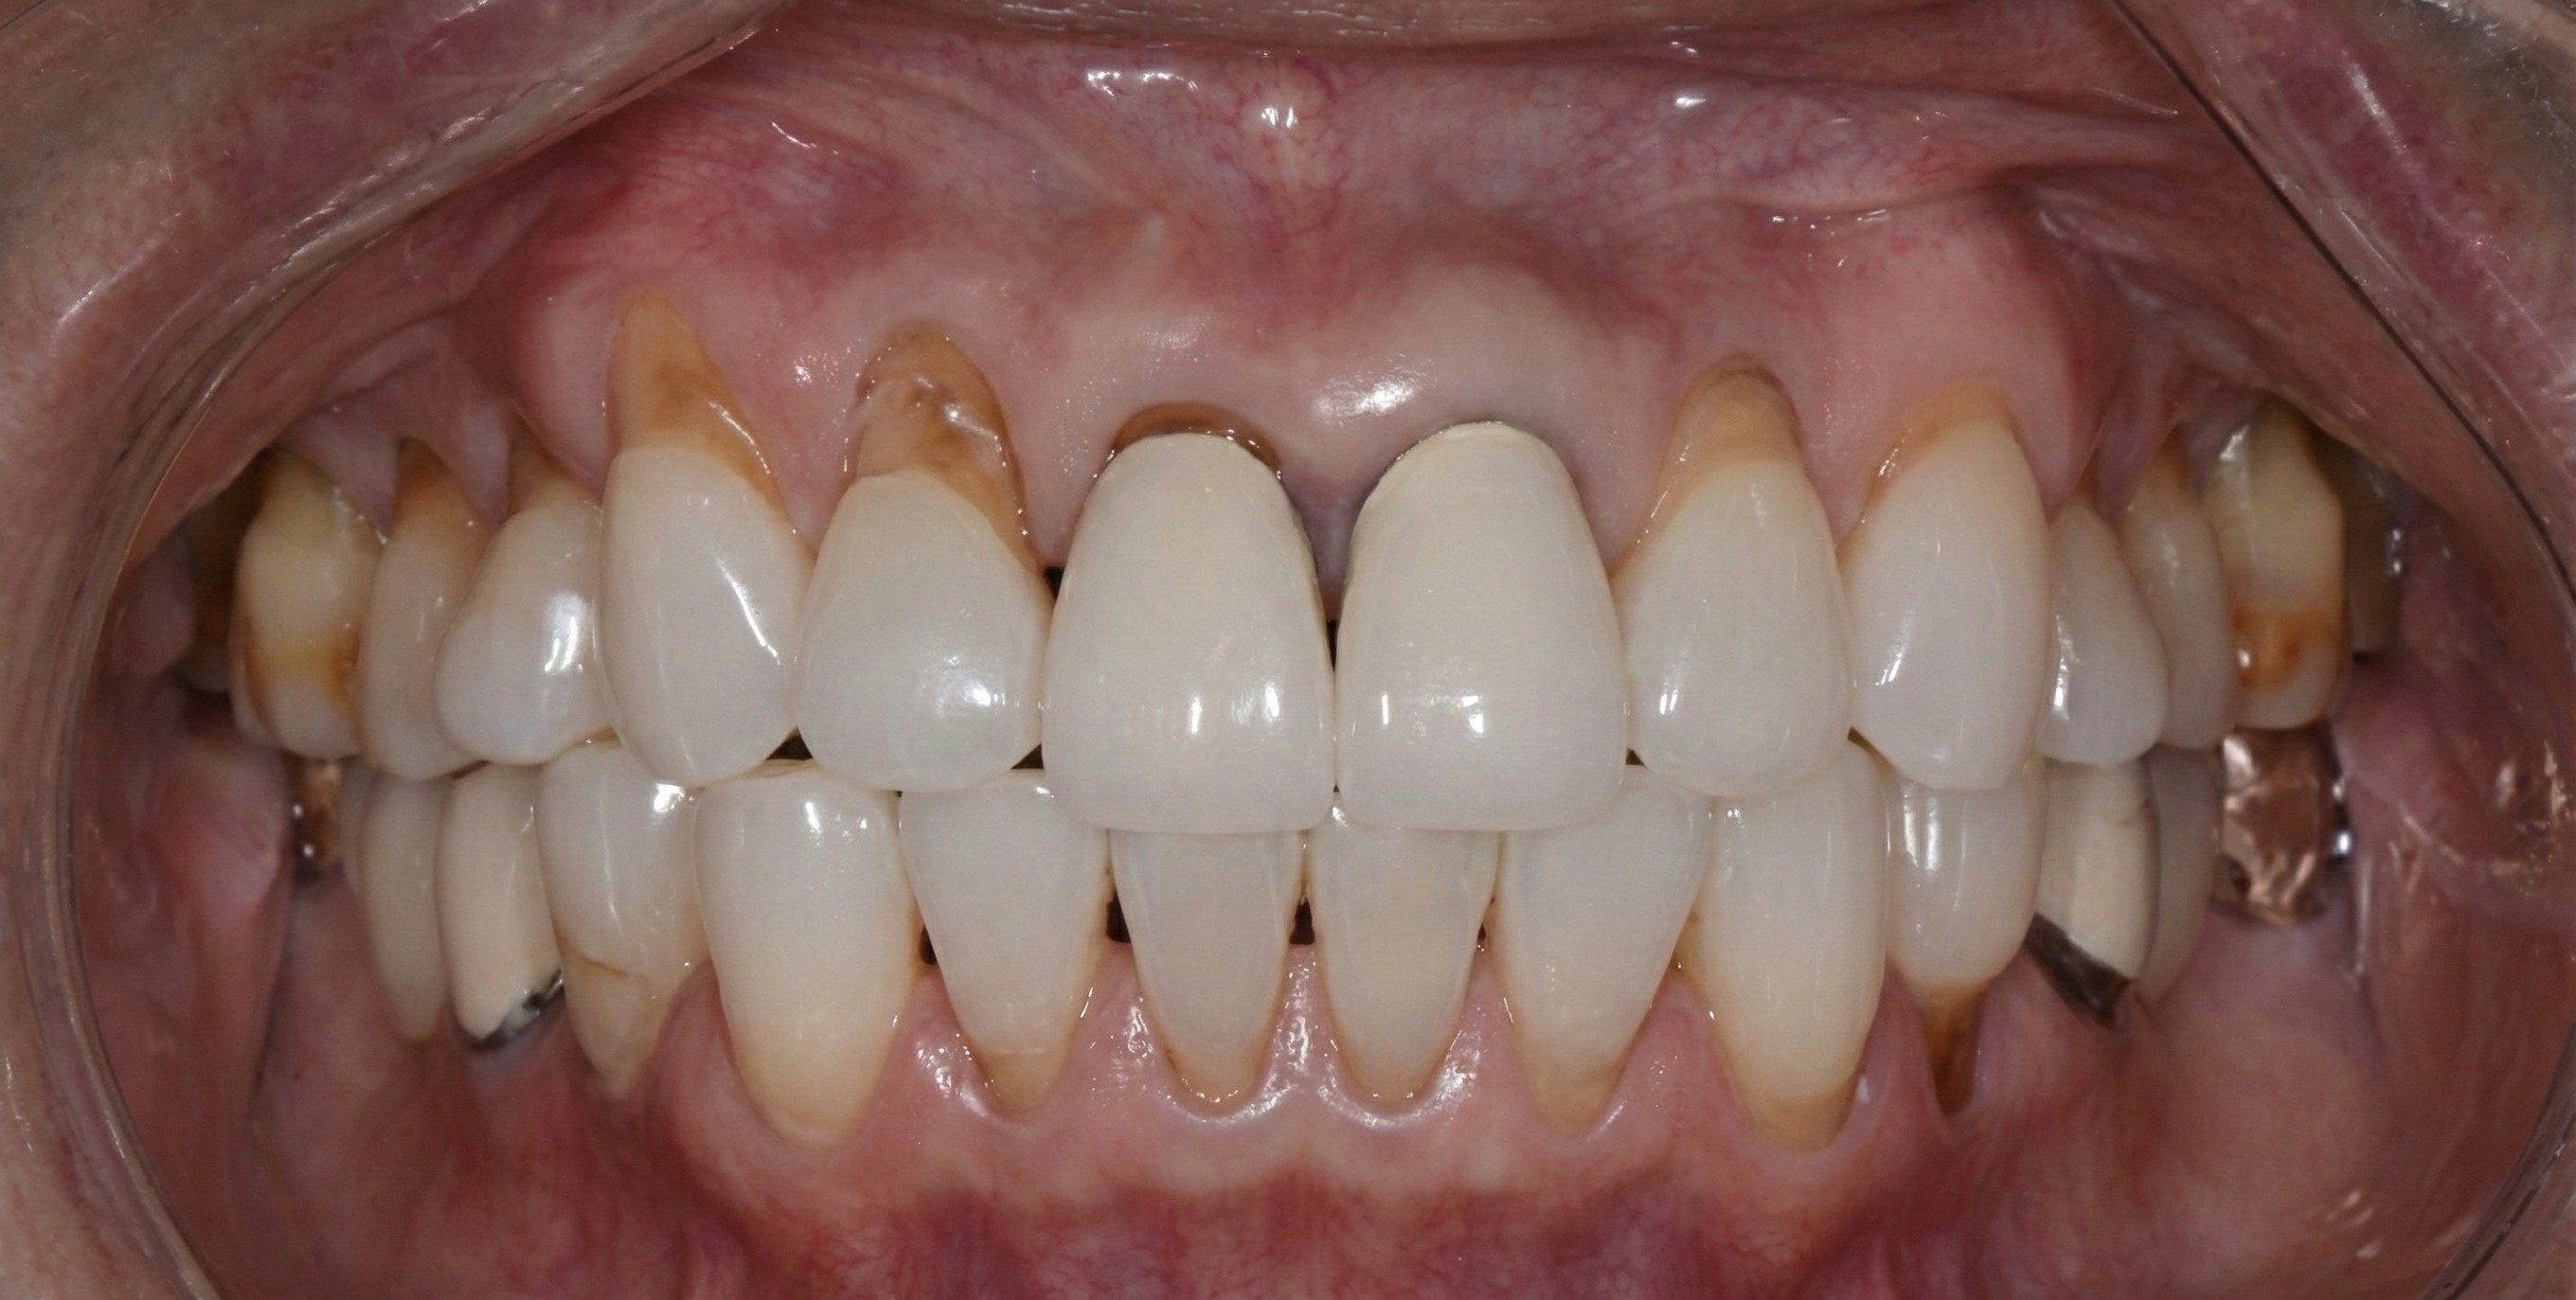

Pinhole® Gum Rejuvenation

Pinhole® Surgical Technique

Generalized Recession

Challenge: Generalized recession exposing root surfaces, leading to dentinal hypersensitivity and esthetic compromise.

Solution: Pinhole® Surgical Technique (PST). A minimally invasive, scalpel-free, and suture-free procedure to advance tissue.

Outcome: 100% root coverage achieved generalized. Stable, thick keratinized tissue band with immediate cosmetic improvement.